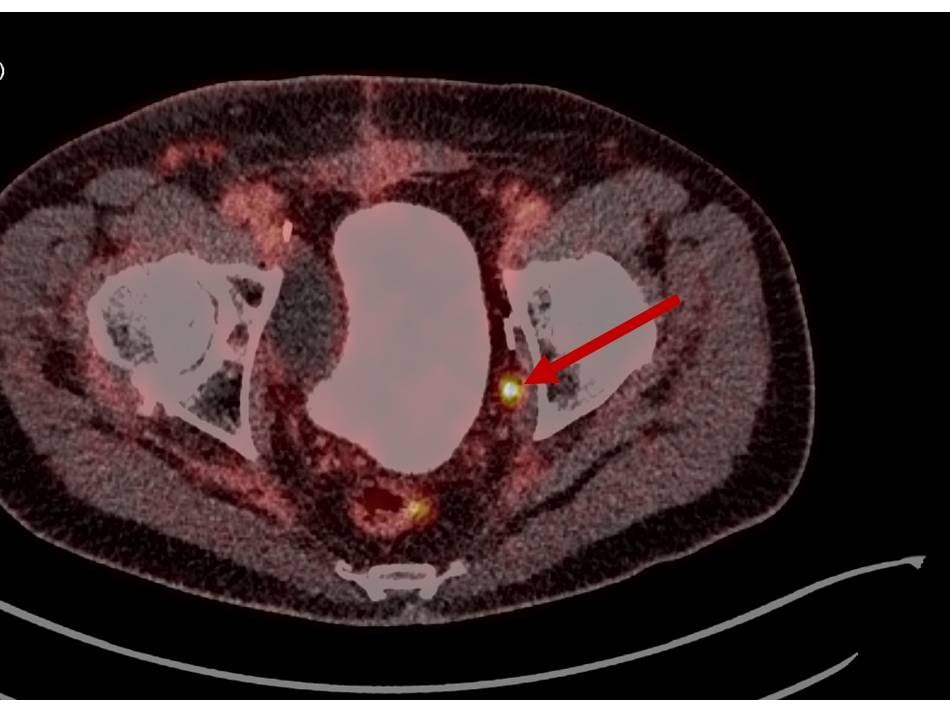

Moderne Bildgebungsverfahren ermöglichen die Erkennung von Tumoren früher und wesentlich genauer. So müssen seltener Biopsien durchgeführt werden und auch die Zahl der OPs und Therapien reduziert sich. Wann MRT und wann PSMA-PET/CT zum Einsatz kommen, erklären die Chefärzte der Nuklearmedizin und Radiologie von zwei Mönchengladbacher Krankenhäusern.

Moderne Bildgebungsverfahren ermöglichen die Erkennung von Tumoren früher und wesentlich genauer. So müssen seltener Biopsien durchgeführt werden und auch die Zahl der OPs und Therapien reduziert sich. Wann MRT und wann PSMA-PET/CT zum Einsatz kommen, erklären die Chefärzte der Nuklearmedizin und Radiologie von zwei Mönchengladbacher Krankenhäusern. Weiterlesen